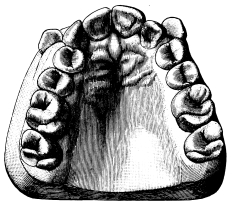

A correct acquaintance with the disposition of the alveoli of the teeth is of importance for skilful and successful operating. Fig. 15 gives a general idea of the appearance of the alveoli, but it is needless to say that a full knowledge can only be really obtained by a careful study of the bones themselves; by this means, too, some idea of the strength of different portions of the alveolar borders can be obtained—a matter of some moment when applying force in the process of removing a tooth from its socket. The points to be specially noted in the maxilla are the thinness of the outer alveolar wall as compared with the inner, the prominence of the canine socket, and the cancellous character of the bone in the region of the third molar. In the mandible the outer alveolar border will be seen to be thinner than the inner, with the exception of that portion in the region of the{13}

Fig. 15.

From the “American System of Dentistry.”

third, and often of the second molar; another fact worthy of attention is that at the posterior portion{14} of the socket of the third molar the bone is moderately dense.